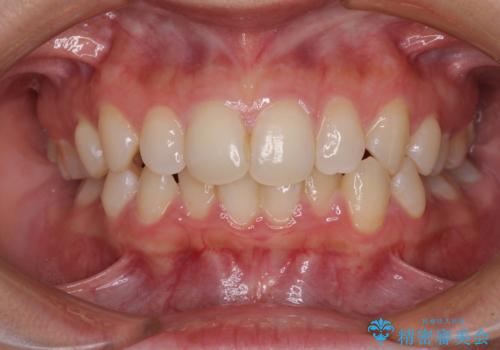

上下のデコボコを治したい インビザラインによる矯正治療